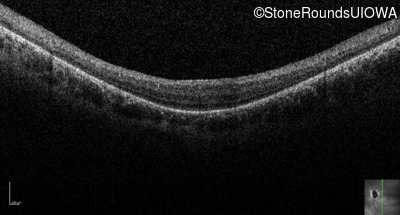

Optical Coherence Tomography - Right - 20/100

Exemplar / OCT Stack

OCT Stack

Optical Coherence Tomography - Left - 20/100